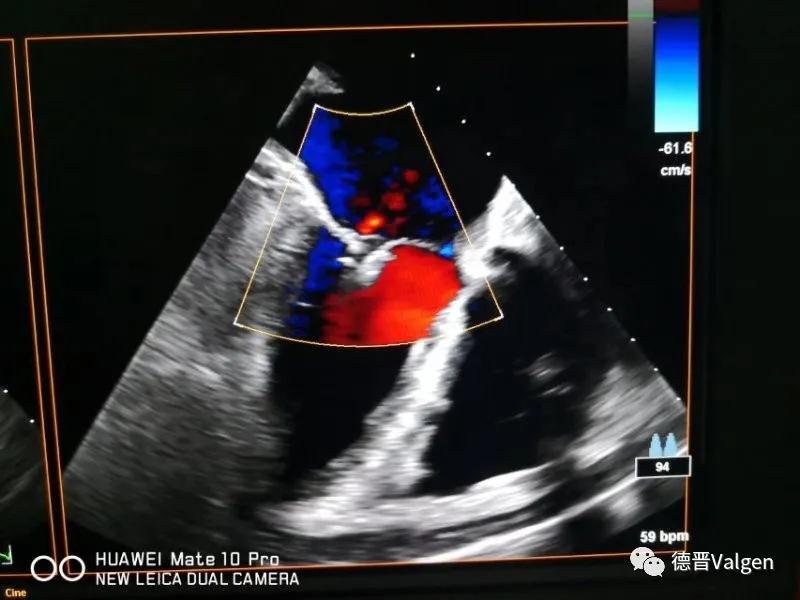

突破!华西医院陈茂教授团队成功开展Dragonfly™手术

德晋医疗专注于结构性心脏病领域尤其是二尖瓣和三尖瓣的相关治疗技术的研发,提供二尖瓣病变系统性解决方案(Tool Box Concept)。德晋医疗曾研发了中国第一款微创介入治疗二尖瓣反流的产品(MitralStitch®),并于2018年1月份成功应用于人体临床。DragonFly™为中国第一款经股静脉二尖瓣缘对缘修复器械,优化的输送系统,使产品可同时应用于三尖瓣介入治疗。德晋医疗成为了国际上唯一具备两种成熟的二尖瓣介入修复器械的公司。德晋医疗的其他二尖瓣和三尖瓣相关器械也在研发当中,公司致力于创新型二尖瓣微创介入治疗全套技术研发,全力推动结构性心脏病治疗领域的发展,让中国智造,惠及世界。